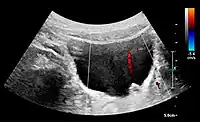

Figure 6. Complex cyst with thickened walls and membranes in the lower pole of an adult kidney. Measurements of kidney length and the complex cyst on the US image are illustrated by '+' and dashed lines.[1]